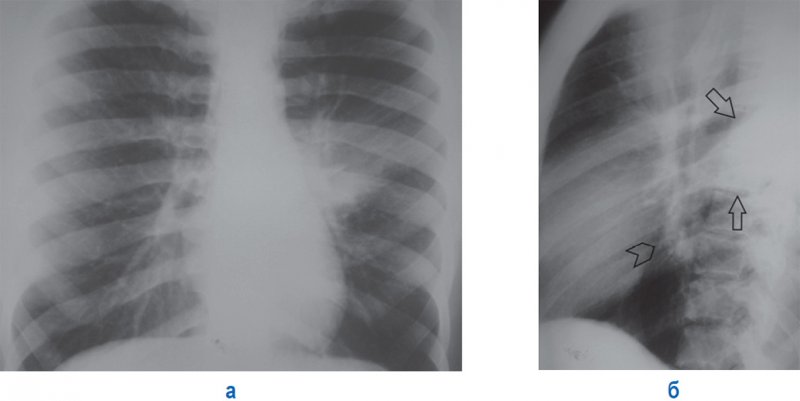

Правосторонняя сегментарная пневмония в верхней доле

Рисунок 3. Правосторонняя сегментарная пневмония в верхней доле. А – рентгенограмма прямой проекции. Б – фрагмент рентгенограммы боковой проекции. На снимках отмечается небольшой участок инфильтрации в S3 верхней доли справа (на снимке Б он отмечен стрелками), в местах расположения возле междолевой плевры четкие контуры